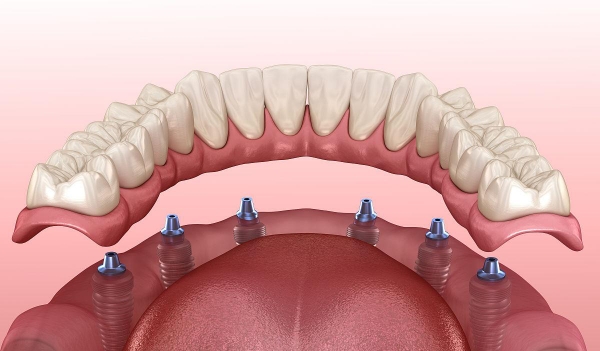

4. 于都美康口腔:专注疑难种植,骨条件差也能种

为什么推荐:专门做复杂种植,比如骨量不足、全口无牙的患者。医生经验比较丰富,成功概率高。

真实实例:我表姐骨量少,跑了3家诊所都说不能种,之后在美康口腔种成功了!

江西于都哪个店种植牙好优势:疑难种植医生、成功概率高、方案个性化

价格参考:种植牙4500元起(美国皓圣)